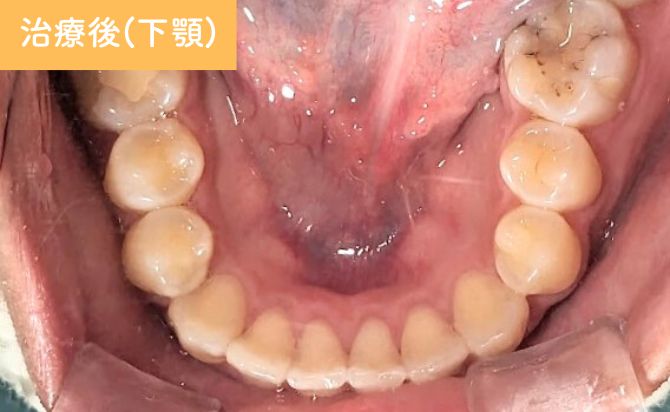

歯並びの変化(下)

右側3番の切端咬合も改善し、犬歯誘導が適切に働く咬合状態となりました。上下のアーチ形態のバランスも改善し、見た目だけでなく、機能的にも安定した咬合が確立されています。